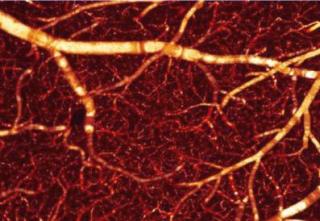

Optical coherence Doppler tomography shows how cocaine damages cerebral blood vessels.

Optical coherence Doppler tomography (ODT) is one promising answer, able to deliver quantitative visual information about the behavior of blood vessels, and provide valuable functional data about what happens to them under different stimuli and conditions.

The combination can produce high-resolution tomographic images of static and moving elements in a blood vessel simultaneously; and, crucially, combines that high resolution with a better field of view (FOV) than other methods provide.

Acute cocaine uptake may lead to the shut down of small capillaries in the brain, while long-term abuse can cause permanent vascular damage. The team used mice as an animal model to determine how effective ODT could be at spotting these and other drug-related changes.

It found that CBFv dramatically decreased after 30 days continuous cocaine administration, as some vessels started to constrict and some others shut down altogether. At the capillary level, flow velocity become extremely slow - so much so that it could hardly be detected by ODT, suggesting a severe shortage of blood supply and consequent poor delivery of oxygen to the brain cells.

"Owing to ODT’s high spatial resolution and large FOV, we are able to visualize for the first time the heterogeneous CBFv change in response to acute and chronic cocaine administration," commented Pan. "This would not have been possible using traditional imaging modalities such as fMRI or PET, which fail to differentiate individual vessels. And importantly, it is a track-free approach without any injection of fluorescence dye, so potential artifacts arising from drug interactions are avoided."